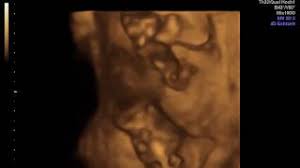

3d Ultraschall Bei 19 0 20 Ssw Youtube

3d Ultraschall Bei 19 0 20 Ssw Youtube from i.ytimg.com